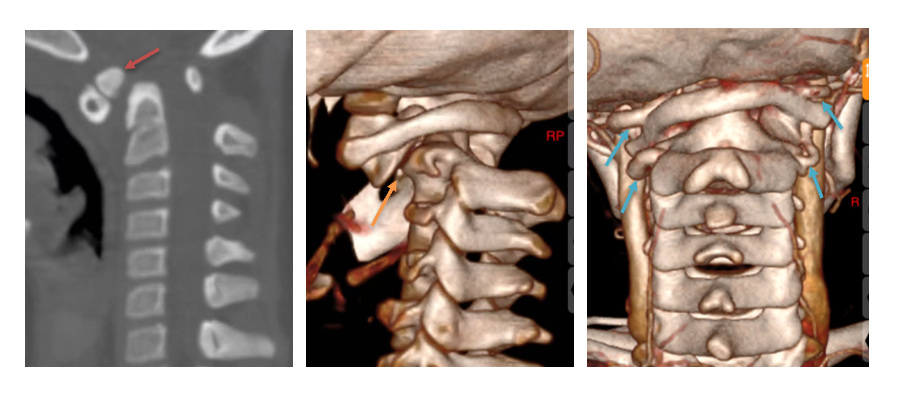

面对挑战,许正伟主任团队在西安市红会医院脊柱病医院院长闫亮、学科带头人贺宝荣主任带领下,为康康制定了周密的个性化方案。术前,三维椎动脉CTA精准“测绘”出脱位的详情与椎动脉的走向。由于患儿无法配合常规牵引,团队决定在术中实施高难度的颅骨牵引复位。

手术日,在麻醉与神经电生理监测团队的全程护航下,主刀医生许正伟主任首先巧妙利用颅骨牵引,为完全脱位的关节实现了初步松解与部分复位。随后,在高端术中导航系统(S8)的实时引导下,将椎弓根螺钉精准、安全地置入寰椎与枢椎的微小椎弓根内。利用螺钉提供的稳固杠杆,脱位的关节被轻柔而坚定地“推”回了正常解剖位置,实现了完美复位。最后,取自患儿自身的髂骨块被植入后方,为永久性骨融合打下基础。